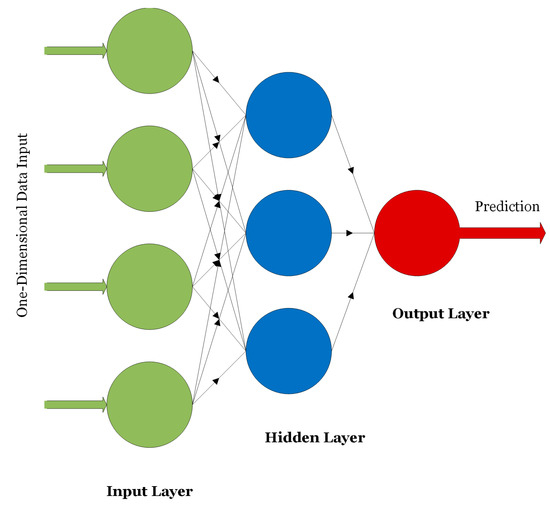

On the other hand, unsupervised methods aim at clustering data into groups or creating association rules that better describe the underlying data structures without the need of expert-level labels during the training process of the models. Examples include K-Means clustering [13], autoencoders [14], deep belief networks [15], and self-organizing maps [16]. ANNs, CNNs, RNNs, and autoencoders are widely used in medical applications. ANNs were first introduced in 1958. The network, as shown in Figure 1, consists of an input layer, one or several hidden layers, and an output layer providing a prediction [6].

Figure 1.

An example of an ANN.

ANNs are used for classifying or analyzing one-dimensional signals such as speech or EEG signals. The nodes of the network are fully connected and the connections between the nodes are strengthened or weakened using weights updated via the backpropagation algorithm. CNNs are other forms of neural networks that are useful for handling two-dimensional as well as multi-dimensional signals such as digital images and videos. The main advantage of CNNs over ANNs is that CNNs are scalable where the number of learning parameters is independent on the input data size. As shown in Figure 2, CNNs consist mainly of convolutional layers that extract low- or high-level features from different regions of the image. Pooling layers are used to reduce the dimensionality of the extracted features by the convolutional layers and hence reduce the computational complexity of the network. Fully connected layers are deployed at the end of the network for the purpose of classifying the input based on the features generated by the convolutional and pooling layers.